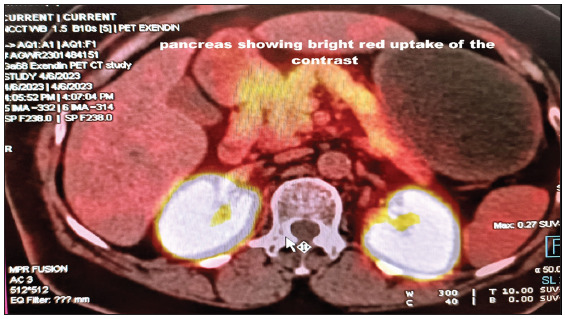

We report a rare and intricate case of nesidioblastosis, marked by hyperinsulinemic hypoglycemia, in a patient with diabetes and chronic kidney disease (CKD). PET-CT imaging and histopathology confirmed the condition, culminating in a comprehensive treatment strategy comprising subtotal pancreatectomy and pharmacotherapy. This case marks the first documented occurrence of nesidioblastosis in a patient with CKD and diabetes. The presence of CKD further complicated the clinical picture, influencing hypoglycemic risk, drug efficacy, insulin clearance, and counter-regulatory mechanisms.